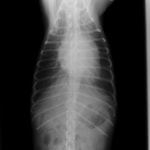

症例:【マルチーズMix 1歳齢 メス】

A:胸部レントゲン写真 正面像

B:胸部レントゲン写真 側面像

左側胸壁よりLevine 4/6の連続性心雑音が聴取された。胸部レントゲン検査において心拡大が認められ、超音波検査においても肺動脈領域に連続的な異常血流が観察された。大学病院を紹介受診され、手術が行われた。現在はACE阻害薬のみの内服で補助的治療を行っている。